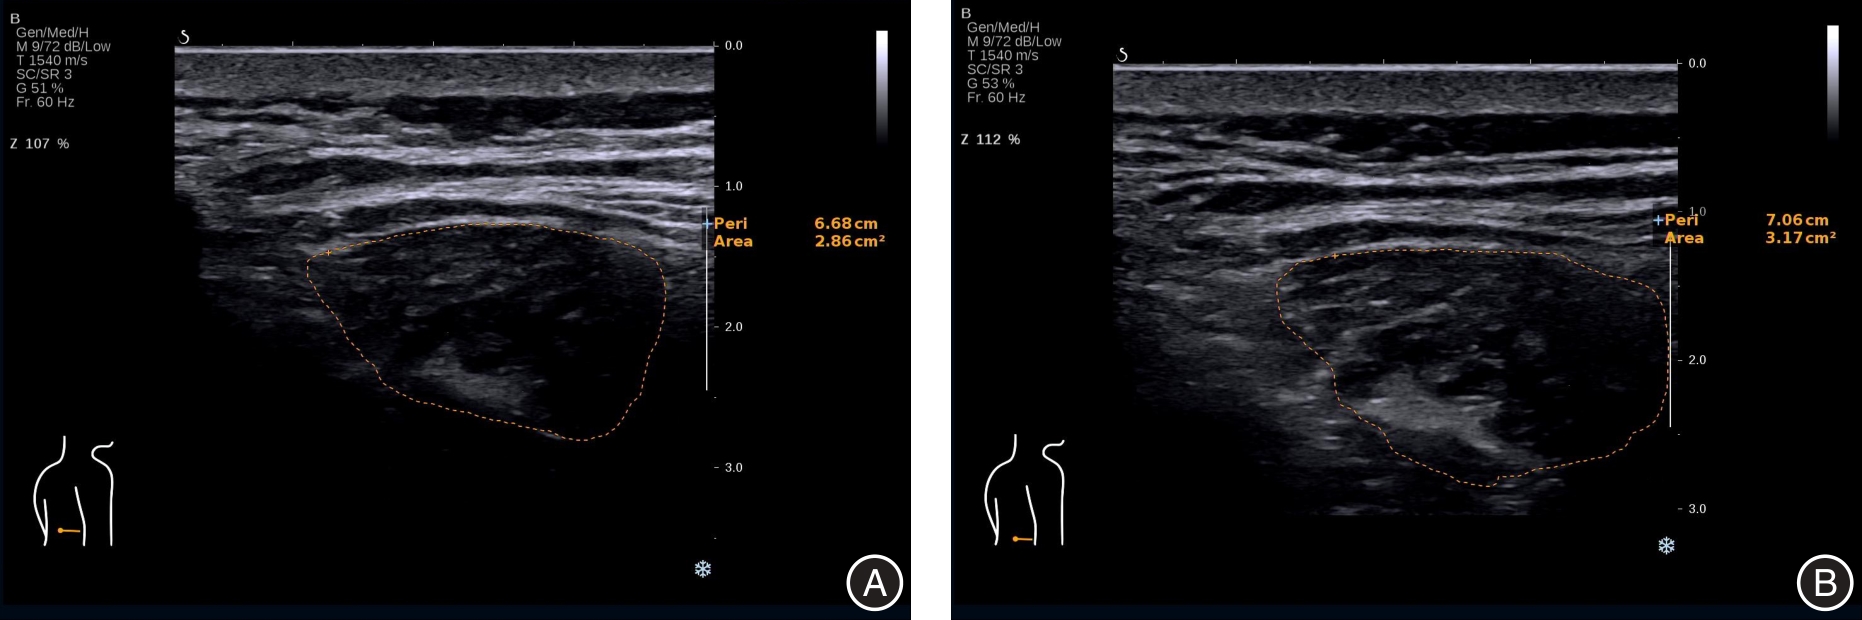

目的 分析四维牵引治疗老年退行性腰椎管狭窄症(DLSS)疗效、腰肌形态学及力学性能的效果。 方法 选择2022年1月至2024年2月广州中医药大学第二附属医院收治的老年DLSS患者按治疗方式分为观察组(肌肉锻炼+四维牵引,40例)和对照组(常规肌肉锻炼,40例)。对照组接受常规肌肉锻炼,观察组接受肌肉锻炼+四维牵引治疗,治疗4周。进行超声多模态检查,比较两组腰肌肌群形态学、力学性能、腰椎活动度、间歇性跛行距离、视觉模拟评分(VAS)、Oswestry功能障碍指数(ODI)。 结果 治疗后,观察组多裂肌厚度、多裂肌周长、多裂肌横截面积、压痛阈、腰椎活动度均大于对照组(P < 0.05),多裂肌剪切波速度(SWV)、多裂肌杨氏模量、肌张力、屈曲伸直比均小于对照组(P < 0.05),间歇性跛行距离长于对照组(P < 0.05)。治疗结束后及随访12个月期间,观察组VAS评分、ODI指数均低于对照组(P < 0.05)。 结论 四维牵引联合肌肉锻炼治疗能有效改善老年DLSS患者的临床症状、肌肉功能和力学性能。

Objective To evaluate the efficacy of four-dimensional traction in elderly patients with degenerative lumbar spinal stenosis (DLSS), focusing on changes in lumbar muscle morphology and mechanical properties. Methods Elderly patients with DLSS admitted to the Second Affiliated Hospital of Guangzhou University of Chinese Medicine from January 2022 to February 2024 were enrolled. Based on the treatment method, they were categorized into the study group (muscle exercise combined with four-dimensional traction, n = 40) and the control group (routine muscle exercise, n = 40). All participants underwent a 4-week treatment regimen and subsequently received multimodal ultrasound examinations. The morphology and mechanical properties of the lumbar muscle group, lumbar range of motion, walking distance in intermittent claudication, Visual Analogue Scale (VAS), and Oswestry Disability Index (ODI) scores were compared between the two groups. Results After treatment, the study group exhibited significantly greater improvements in multifidus muscle thickness, circumference, cross-sectional area, pressure pain threshold, and lumbar range of motion (P < 0.05). In contrast, the shear wave velocity (SWV), Young's modulus, muscle tension, and flexion-extension ratio of the multifidus muscle were significantly lower in the study group (P < 0.05). Additionally, the walking distance in intermittent claudication for the study group was markedly longer (P < 0.05). During the 12-month follow-up period after treatment, the VAS and ODI scores of the study group remained significantly lower (P < 0.05). Conclusion Four-dimensional traction in combination with muscle exercise can effectively alleviate clinical symptoms, enhance muscle function, and improve mechanical properties in elderly patients with DLSS.